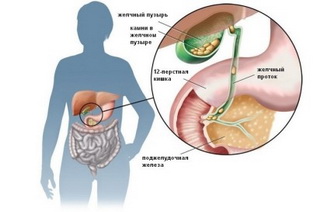

Из-за увеличившегося в размерах живота на 32 неделе беременности женщина быстро устает. Матка выше лонного сочленения на 32 см и подпирает снизу ребра. Живот на 32 неделе беременности мешает женщине лежать, сидеть в одной позе, долго ходить. Из-за стеснения внутренних органов появляются неприятные ощущения в виде изжоги, отрыжки кислым, тошноты или запоров. Несложные рекомендации врача помогают облегчить эти состояния. Может измениться внешний вид и состояние кожи беременной – кожа и волосы становятся сухими, на животе кожа натягивается и зудит. На бедрах, на животе в области пупка и на груди иногда могут появиться растяжки (по-другому их называют стриями).